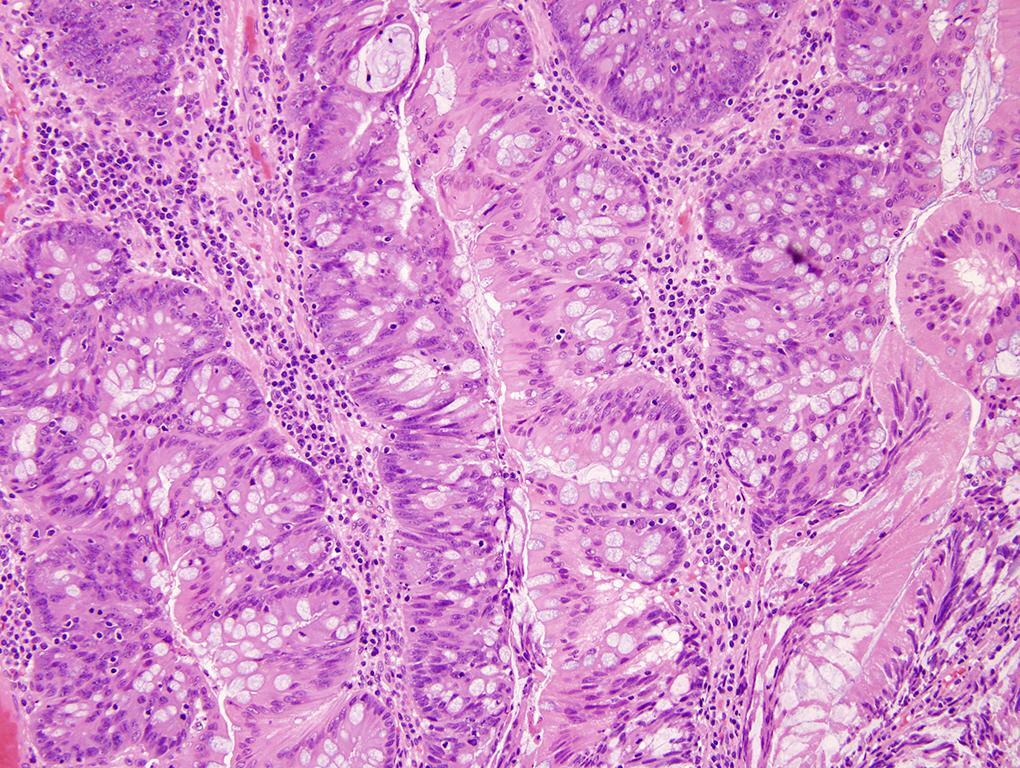

Про гистологию

Про гистологию 84 фотографий